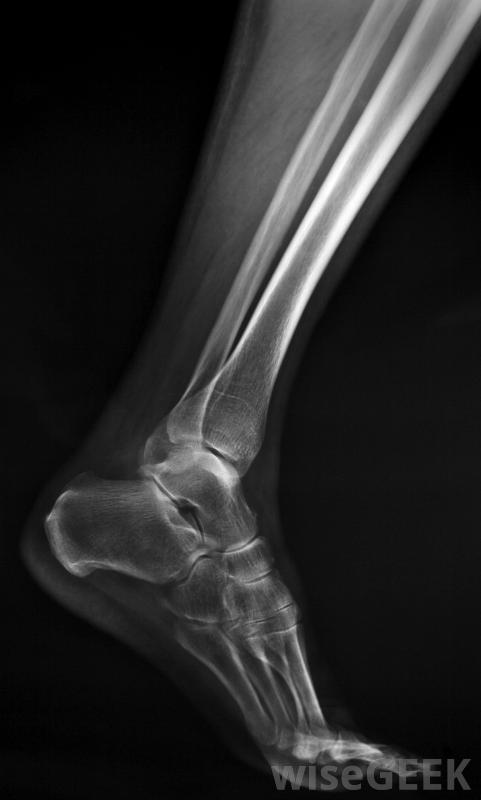

腓骨也被稱為小腿骨之一,位于側面或小腿外側。這又長又細的骨頭鉤在脛骨上,從膝蓋下一直延伸到腳踝。它與較重的鄰近脛骨的連接方式使這兩塊骨頭看起來像一個鉤子或安全別針。雖然脛骨承受著身體的重量,并且在某種程度上獨立于腓骨,但較粗的骨頭發生骨折可能會同時損傷腓骨。腓骨不能承受重量,固定腓骨板可為該骨提供必要的額外支撐,以確保正常愈合。

腓骨鋼板的放置取決于骨折的位置和嚴重程度。換句話說,整個腓骨或僅部分腓骨可能涉及電鍍技術。用于腓骨板的薄金屬條與骨平行放置,并直接擰入骨中。然后在腿外側放置石膏幾個星期,以確保腿保持不動。在許多情況下,腓骨板即使在完全愈合后仍然與骨頭掛鉤。